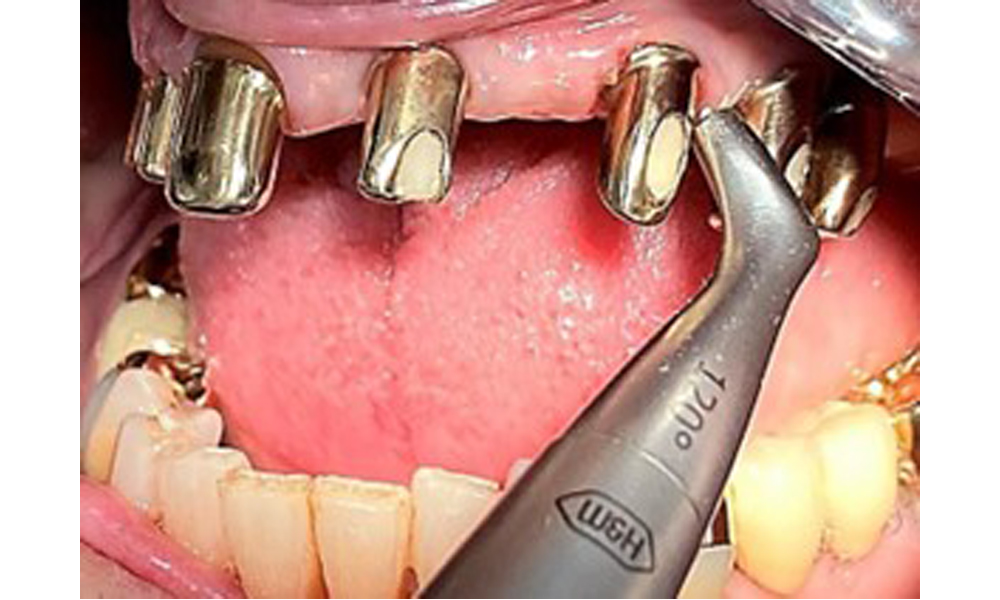

The dental findings are as follows: Combined removable implant and tooth-supported telescopic prostheses on implants 15, 13, 21, 23, 24, 25 and tooth 11 (Fig. 1, Fig. 2, Fig. 3). The patient was fitted with a fixed mandibular denture. Adequate bridges were present over 37 to 34 and 45 to 47 (Fig. 4), the crown margins were intact and there were no active caries. A composite filling with a marginal gap was present on tooth 43. There was mandibular gingival recession, exposing 1 to 3 mm of root surface. This also applies to 11.

Occlusal view of the mandible.

Fig. 4: Occlusal view of the mandible.

Sonic/ultrasonic, or conventional manual instruments may be used to remove calculus and concretions present on the natural teeth (8). Titanium or plastic curettes (Fig. 10), or a plastic or PEEK attachment (Fig. 11) during ultrasonic treatment, should be used to remove mineralized plaque from implants to avoid damaging the implant surfaces.